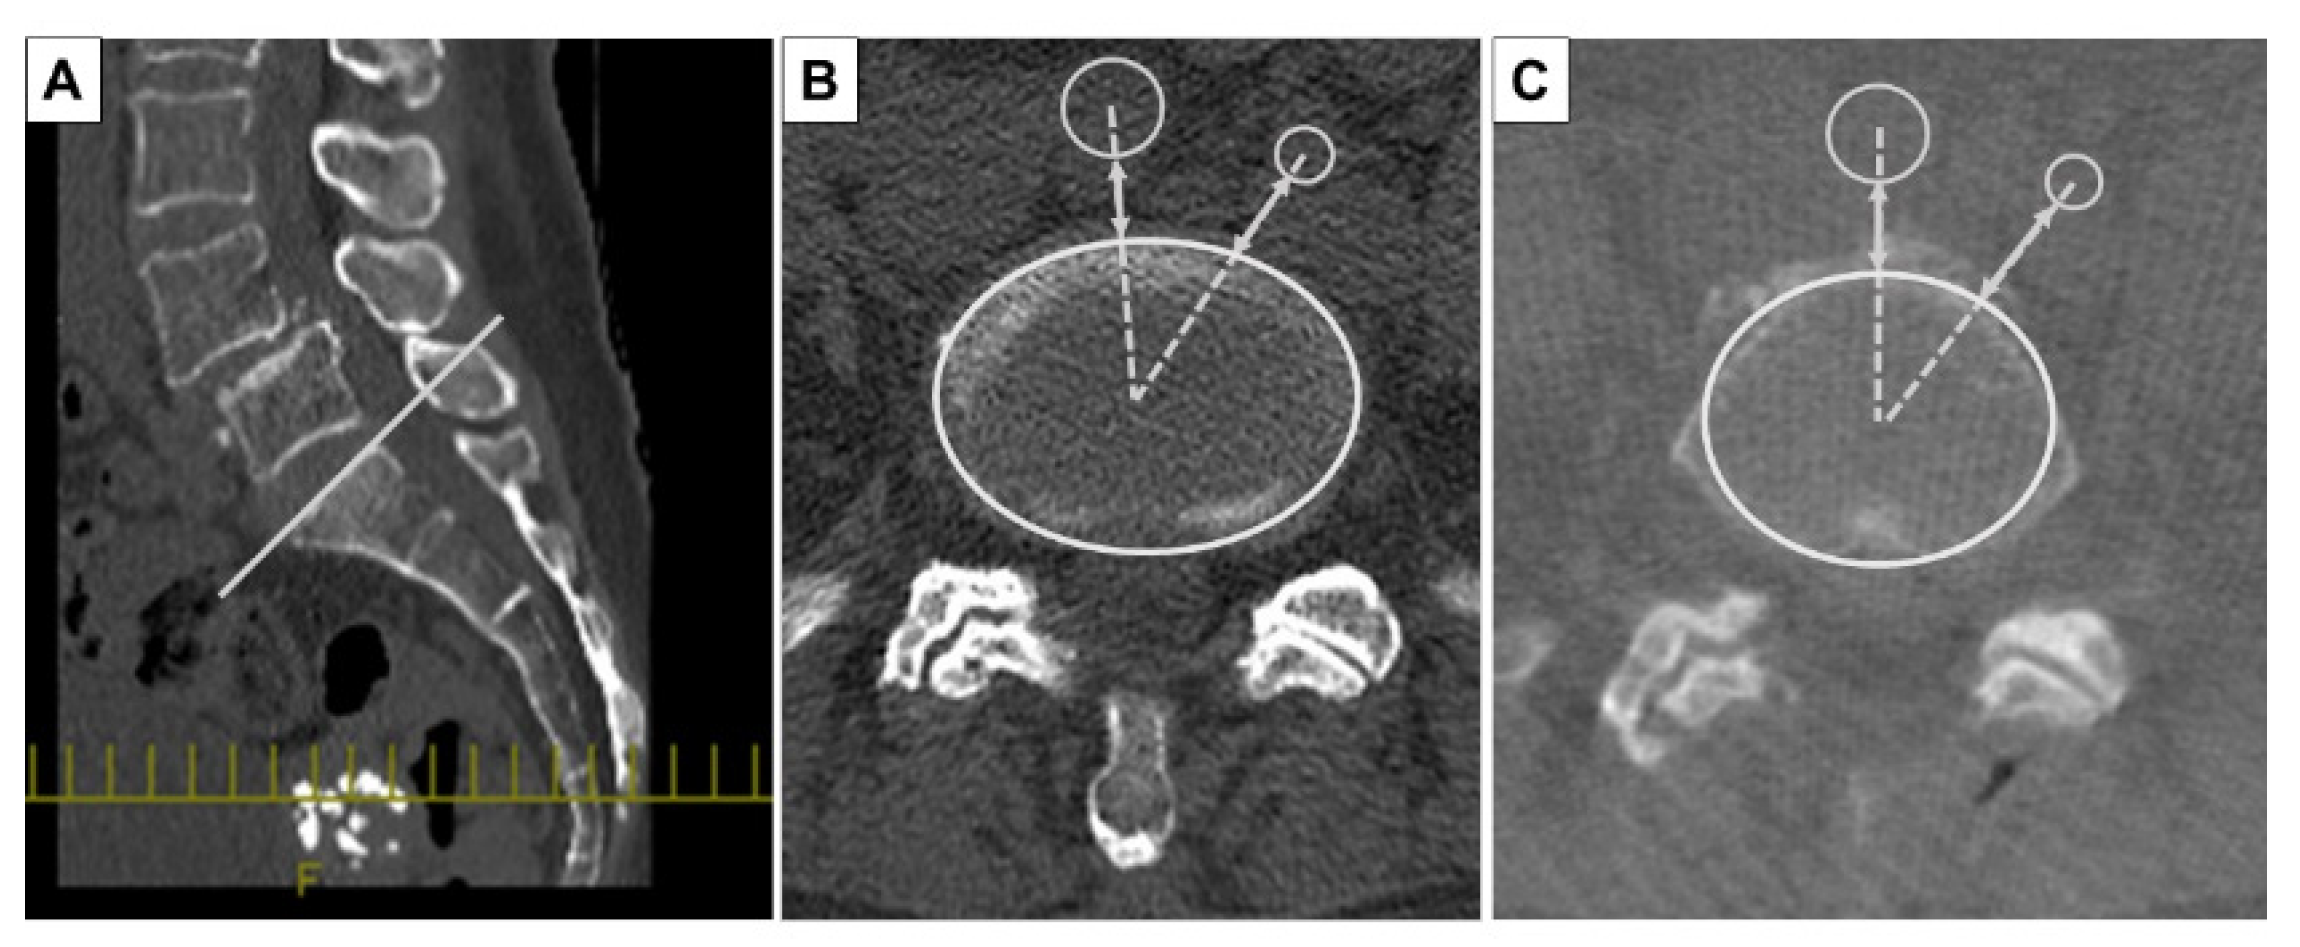

2.2. Evaluation Method of Preoperative and Intraoperative CT Images